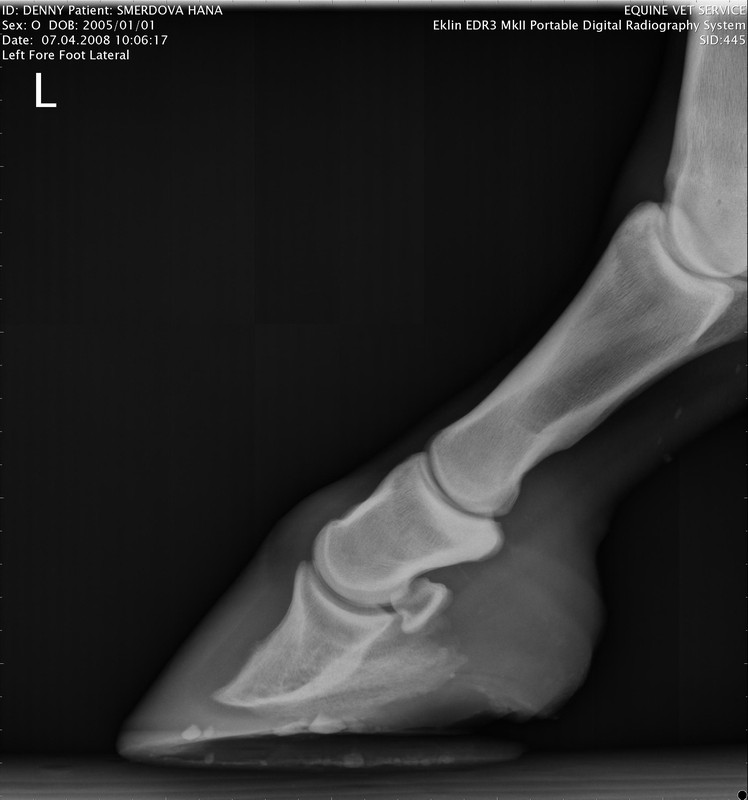

levá přední

RTG Levá přední (07.04.2008)